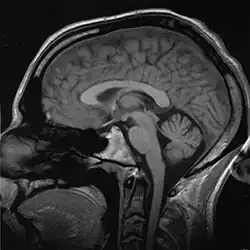

Biomechanics

Biomechanics is the study of the structure and function of the mechanical aspects of biological systems, at any level from whole organisms to organs, cells and cell organelles,[4] using the methods of mechanics.[5]